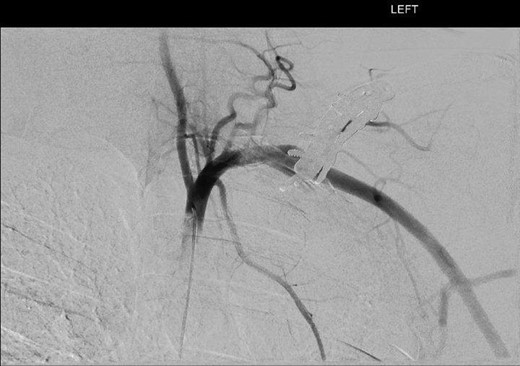

On examination, there was an obvious pulsatile mass posterior to the left clavicle. The perpendicular plates were palpable, with prominent screws. At the time, all upper limb pulses were present with no signs of embolic disease. Neurological examination was also unremarkable. A recent Doppler ultrasound suggested that a plate fixation screw was impinging on the subclavian artery wall, causing increased wall thickness. Computer tomographic angiography (CTA) depicted a left subclavian artery pseudoaneurysm, yet there was significant metalware artefact. Thus, digital subtraction angiography (DSA) was booked (Figures 1 and 2). Yet, prior to undergoing this, he was admitted with sudden worsening of left arm pain and paraesthesia associated with movement despite a viable arm with present distal pulses.

DSA oblique view illustrating fusiform left subclavian pseudoaneurysm.

Digital subtraction angiography via the right common femoral artery (CFA) was performed depicting fusiform aneurysmal dilatation of the mid left subclavian artery posterior to the clavicular plates and screws. Further, a focal area of irregularity was noted along the inferior aspect of the artery at the distal aspect of the aneurysm. On the dynamic study with arm in abduction there was significant compression of the artery by prominent clavicular screws at the site of the pseudoaneurysm.